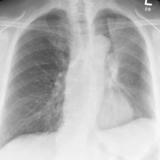

LUL Collapse Case 2 PA

Date: 02/19/2004

Views: 3757